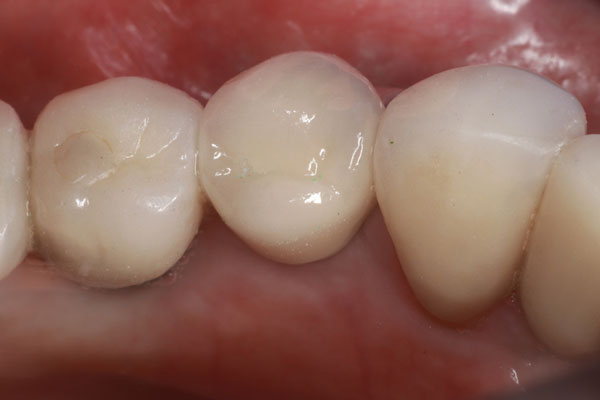

Un paciente se presentó con un diente roto (es decir, el diente No. 28) que requirió tratamiento de conducto. Hubo una pérdida significativa de estructura dental; por lo tanto, se consideró necesario un tratamiento posterior y central para sostener una corona (Figura 1). El paciente fue anestesiado y se excavó cualquier caries restante. Después de obtener, evaluar y medir una radiografía, se utilizó un taladro para eliminar aproximadamente dos tercios de la longitud del material de obturación del conducto radicular (Figura 2). Se tomó otra radiografía para confirmar que la profundidad alcanzada era correcta. A continuación, se probó primero el sistema de poste ajustable único (Splendor SAP, Angelus) sin el manguito para determinar si estaba completamente asentado (Figura 3). Luego se probó con el manguito y se consideró que encajaba bien (Figura 4).

Imagen 10. Vista oclusal de la corona asentada final.